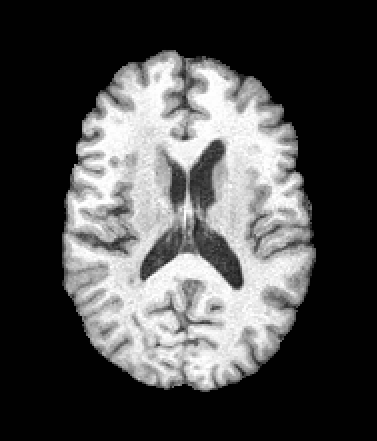

A trained MetaVoxel model can be unconditionally sampled by drawing Gaussian or categorical noise for each variable at timestep , and iteratively apply the denoising network until reaching . Unlike conventional diffusion models that focus solely on image generation, MetaVoxel can generate coherent synthetic patient profiles from the joint distribution , as shown in Figure 2.

| Age: 64.0 | Age: 53.8 | Age: 70.9 | Age: 76.9 |

| Sex: Male | Sex: Female | Sex: Female | Sex: Male |

![]() |

| Age: 80.9 | Age: 77.7 | Age: 73.2 | Age: 84.6 |

| Sex: Male | Sex: Female | Sex: Female | Sex: Female |